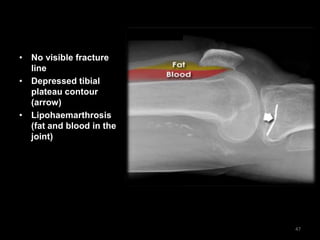

Tibial plateau fracture -

Lateral

• No visible fracture

line

• Depressed tibial

plateau contour

(arrow)

• Lipohaemarthrosis

(fat and blood in the

joint)